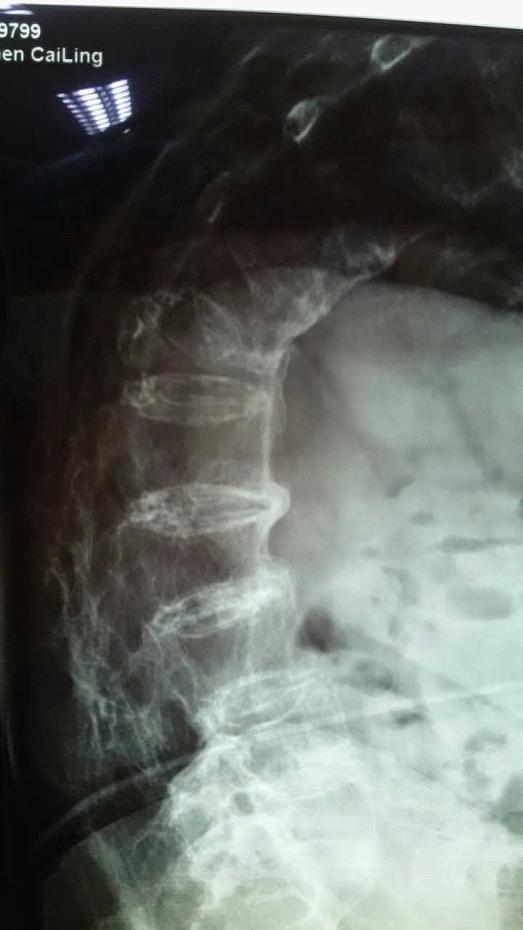

挂号那天,老奶奶刚好挂到博爱医院副院长、脊柱外科主任何建军的专家门诊,何医师认真仔细地询问了患者病情,考虑到病人年龄大,原先有伤痛,于是建议进行全方位体检,还特事特办,根据老人特殊情况跟放射科做好沟通,使之以特别体位顺利完成核磁共振。陈奶奶被诊断为胸11、12椎体压缩性骨折、并伴有严重骨质疏松、强直性脊柱炎。何医师当时设想了两种方案,如果采取保守治疗,陈奶奶将会每日疼痛难忍,而且效果也不好。如果手术,那么她无法象正常人一样俯卧,而且当时拍片出来,显示脊柱扭转、侧弯,骨性标志模糊,这一切都将给手术带来了不可预估的风险及难度。何医师在与家属及本人的反复沟通后。最终决定为患者行微创手术——胸11、12椎体压缩性骨折经皮椎体后凸成形术。

8月24日,这位特殊的病人被推进了手术室,何医师一改常规让病人改俯卧位为侧卧位进行手术,凭借高超的技术与多年的经验,骨折部位经皮穿刺,置入套管,球囊撑开压缩的椎体,在透视下注入3ML骨水泥进行椎体强化。据悉,骨质疏松性椎体压缩骨折常导致患者疼痛、活动受限, 特别是随着老龄人群的增加, 其发病率逐渐升高。经皮椎体后凸成形术是向椎体内注入骨水泥以达到增加椎体强度和稳定性,防止塌陷,解除疼痛,甚至部分恢复椎体高度为目的一种微创脊椎外科技术。与传统的胸腰椎开放式手术相比,具有减少创伤,恢复快的特点。这次手术非常成功,这位特殊的病人让何医师在脊柱外科领域再一次战胜困难,赢得了胜利。